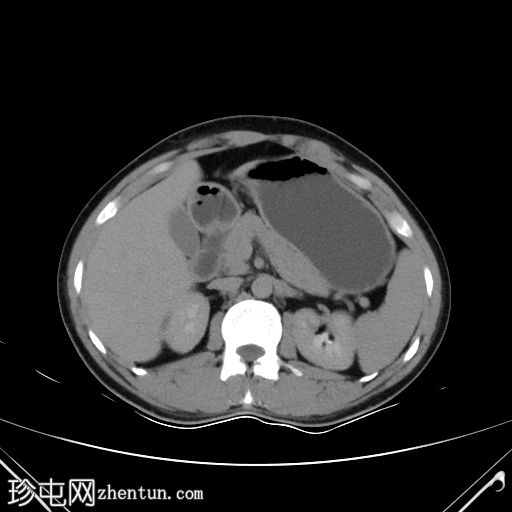

CT

轴位

平扫

右肾存在重复肾盂输尿管畸形,输尿管重复;但输尿管远端显影不佳。膀胱内可能存在两个位置接近的输尿管开口。

可见一局灶性息肉样腔内病变,起源于右侧膀胱输尿管连接处外侧的后外侧壁,增强后轻度强化。

双肾均可见小结石。

双肾未见肾积水。